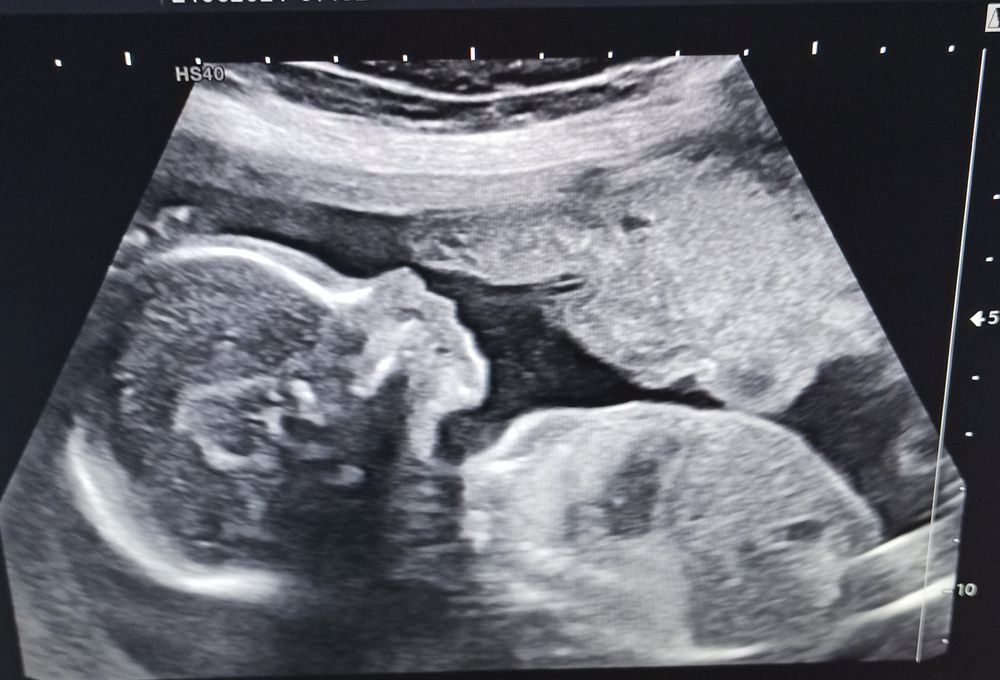

2-ой УЗИ скрининг + ЭХО КГ

Пессарий, ИЦНСегодня 24 июня с малышом всё хорошо, весит 364 грамма, но вот шейка матки подкачала, укоротилась - 18 мм, преоткрыт зев на 6 мм, плацента низко почему то стала, хотя была высоко. Позвонила врачу в женскую консультацию, она на электронную почту переслала направление в Перинатальный центр Середавина на госпитализацию, просидела там 4 часа в очереди, а корпус для маленьких сроков беременности закрыли сегодня на помывку, в результате меня перенаправили в Династию в Самаре, там мне прокапали Гинипрал, назначили вагинально Утрожестан 200 2 раза в день, сказали, сначала обследуют, выяснят причину укорочения шейки, а потом поставят Пессарий. Теперь я как хрустальная ваза боюсь вставать. Боялась за ребёнка, вдруг какую патологию обнаружат, но тут неожиданно пися подвела. Хорошо, что вовремя обнаружили, ведь меня совсем ничего не беспокоит, если бы не УЗИ, я б и не знала о проблеме.